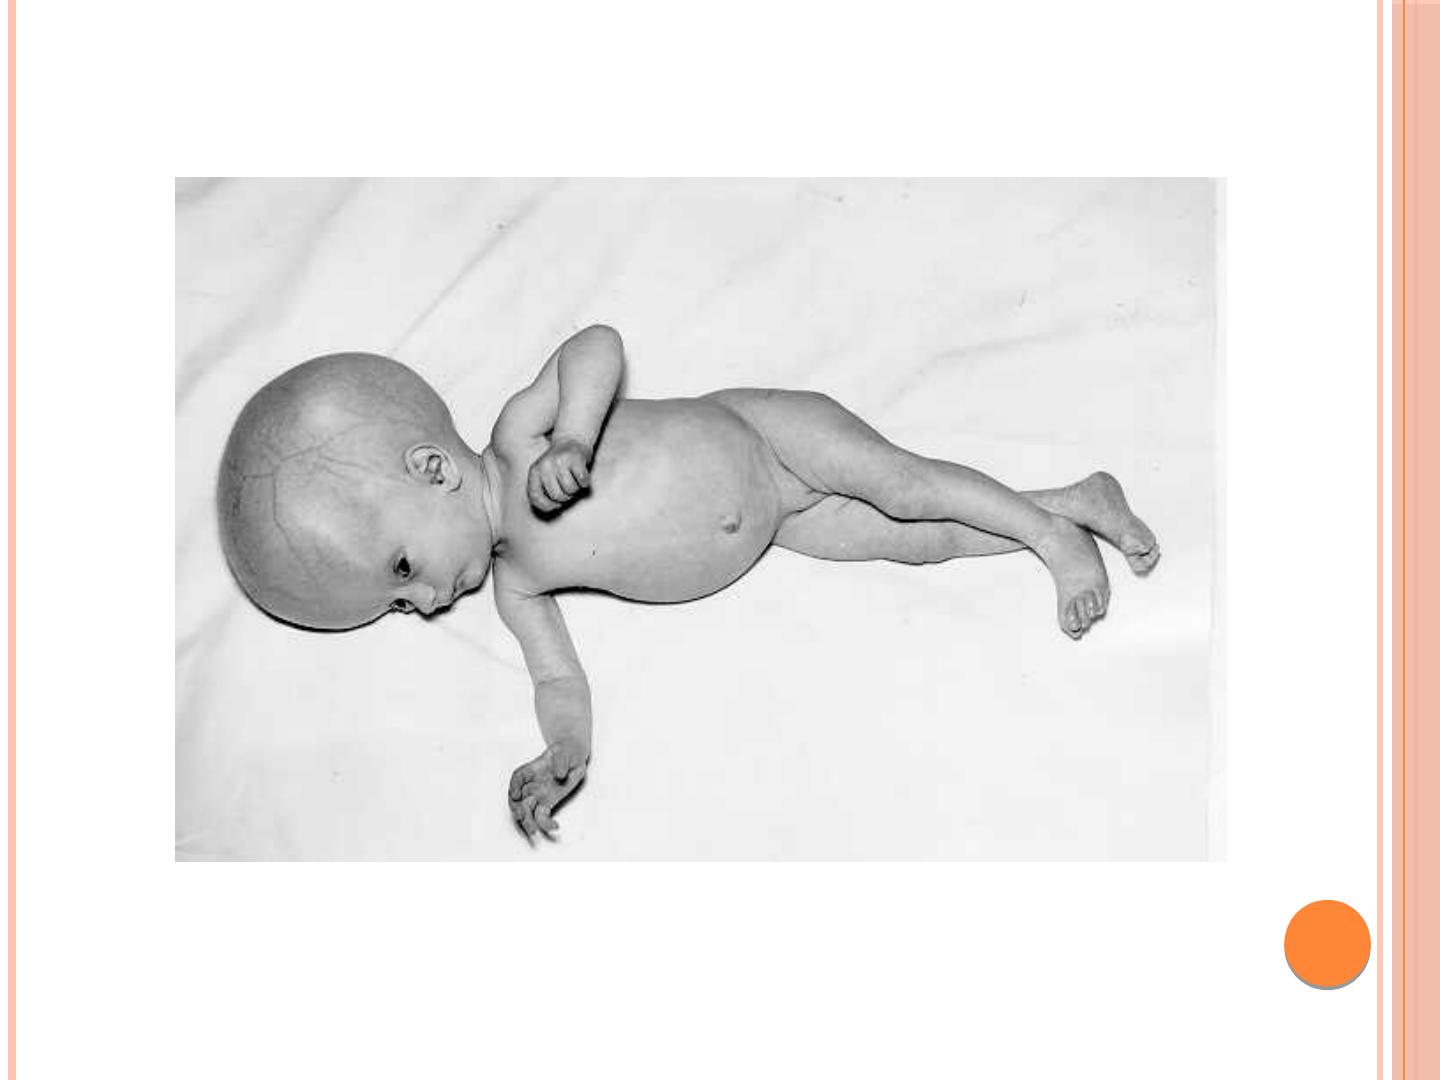

Ewa Majda-Stanisłąwska. Mikroorganizmy powodujące zakażenia wrodzone. TORCH. Toksoplazmoza; Różyczka; Cytomegalia; Herpes simplex wirus typ 2.